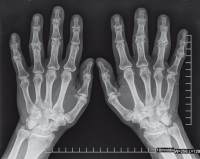

Abbildung 1: Vor bzw. während der Behandlung